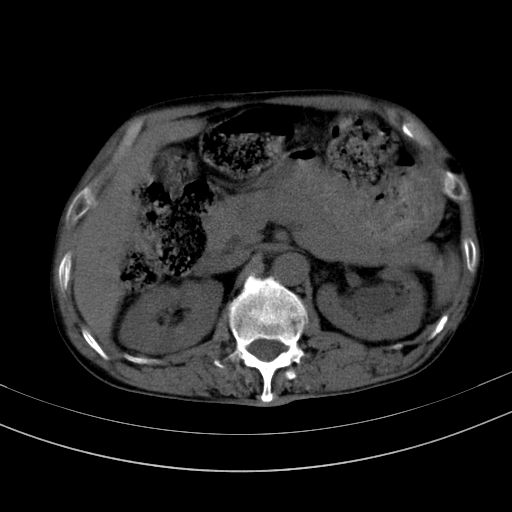

以下是引用dyqct在2010-1-9 17:56:00的发言:[br]考虑:1.双肾囊肿,左肾积水结石、旋转不良。[br] 2.右侧腹直肌血肿或纤维瘤。[br]肠道准备不好。做个增强。